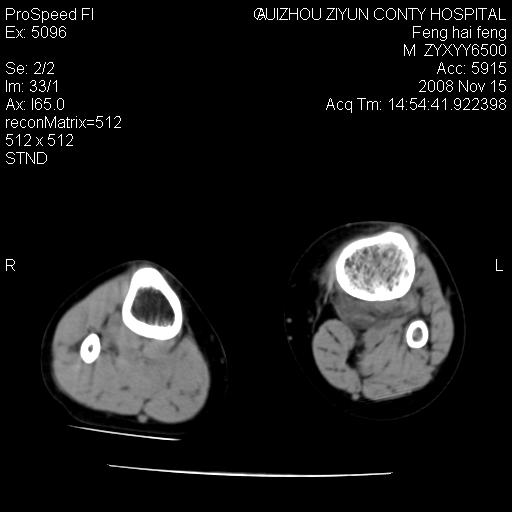

标题: CT16656:M 14Y 左膝关节肿胀一年余。其余病史不详。 [打印本页]

标题: CT16656:M 14Y 左膝关节肿胀一年余。其余病史不详。

考虑左侧髌骨结核;左膝关节滑膜肿胀、增厚,关节囊积液。

左膝滑膜型关节结核可能性大!支持!滑膜型关节结核主要ct表现:关节囊肿胀,积液,关节面见小破坏灶,并见点状死骨!

好大的左腿!考虑左侧髌骨结核,左膝关节滑膜肿胀、增厚,关节囊积液。

左侧髌骨结核;左膝关节滑膜肿胀、增厚,关节囊积液